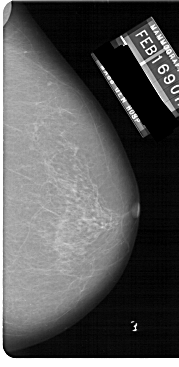

A_1149_1.LEFT_CC

LEFT_CC LINES 5491 PIXELS_PER_LINE 3061 BITS_PER_PIXEL 12 RESOLUTION 43.5 OVERLAY

FILE: A_1149_1.LEFT_CC.OVERLAY

TOTAL_ABNORMALITIES 1

ABNORMALITY 1

LESION_TYPE MASS SHAPE IRREGULAR MARGINS SPICULATED

ASSESSMENT 4

SUBTLETY 2

PATHOLOGY MALIGNANT

TOTAL_OUTLINES 1

BOUNDARY